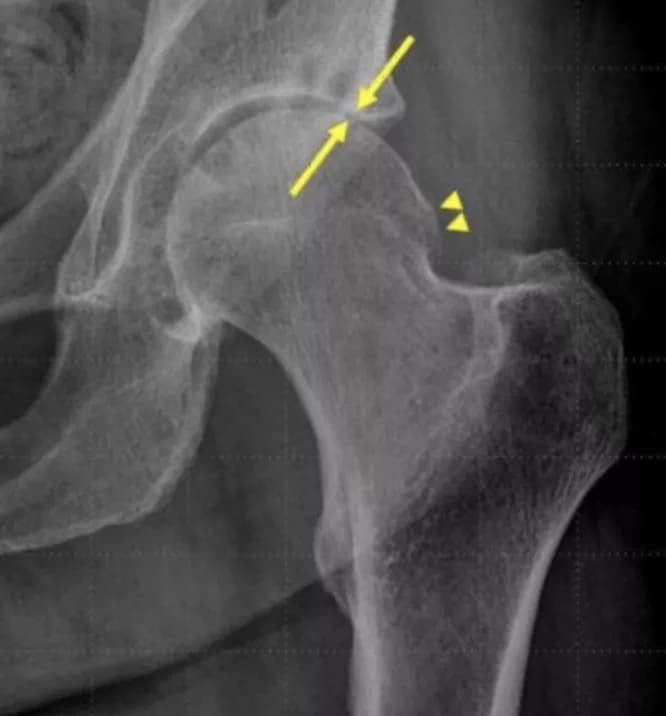

The radiologists reported new osteonecrosis in 22-24 percent of hip injection patients, compared to 5-9 percent in the hip control group and 5 percent in the shoulder injection control group. They observed bone collapse in the head of the femur bone, located at the top of the femur at the articulation with the pelvic bone, in 15-17 percent of hip injection patients, versus 4 percent of hip control patients and 2 percent of shoulder control patients.